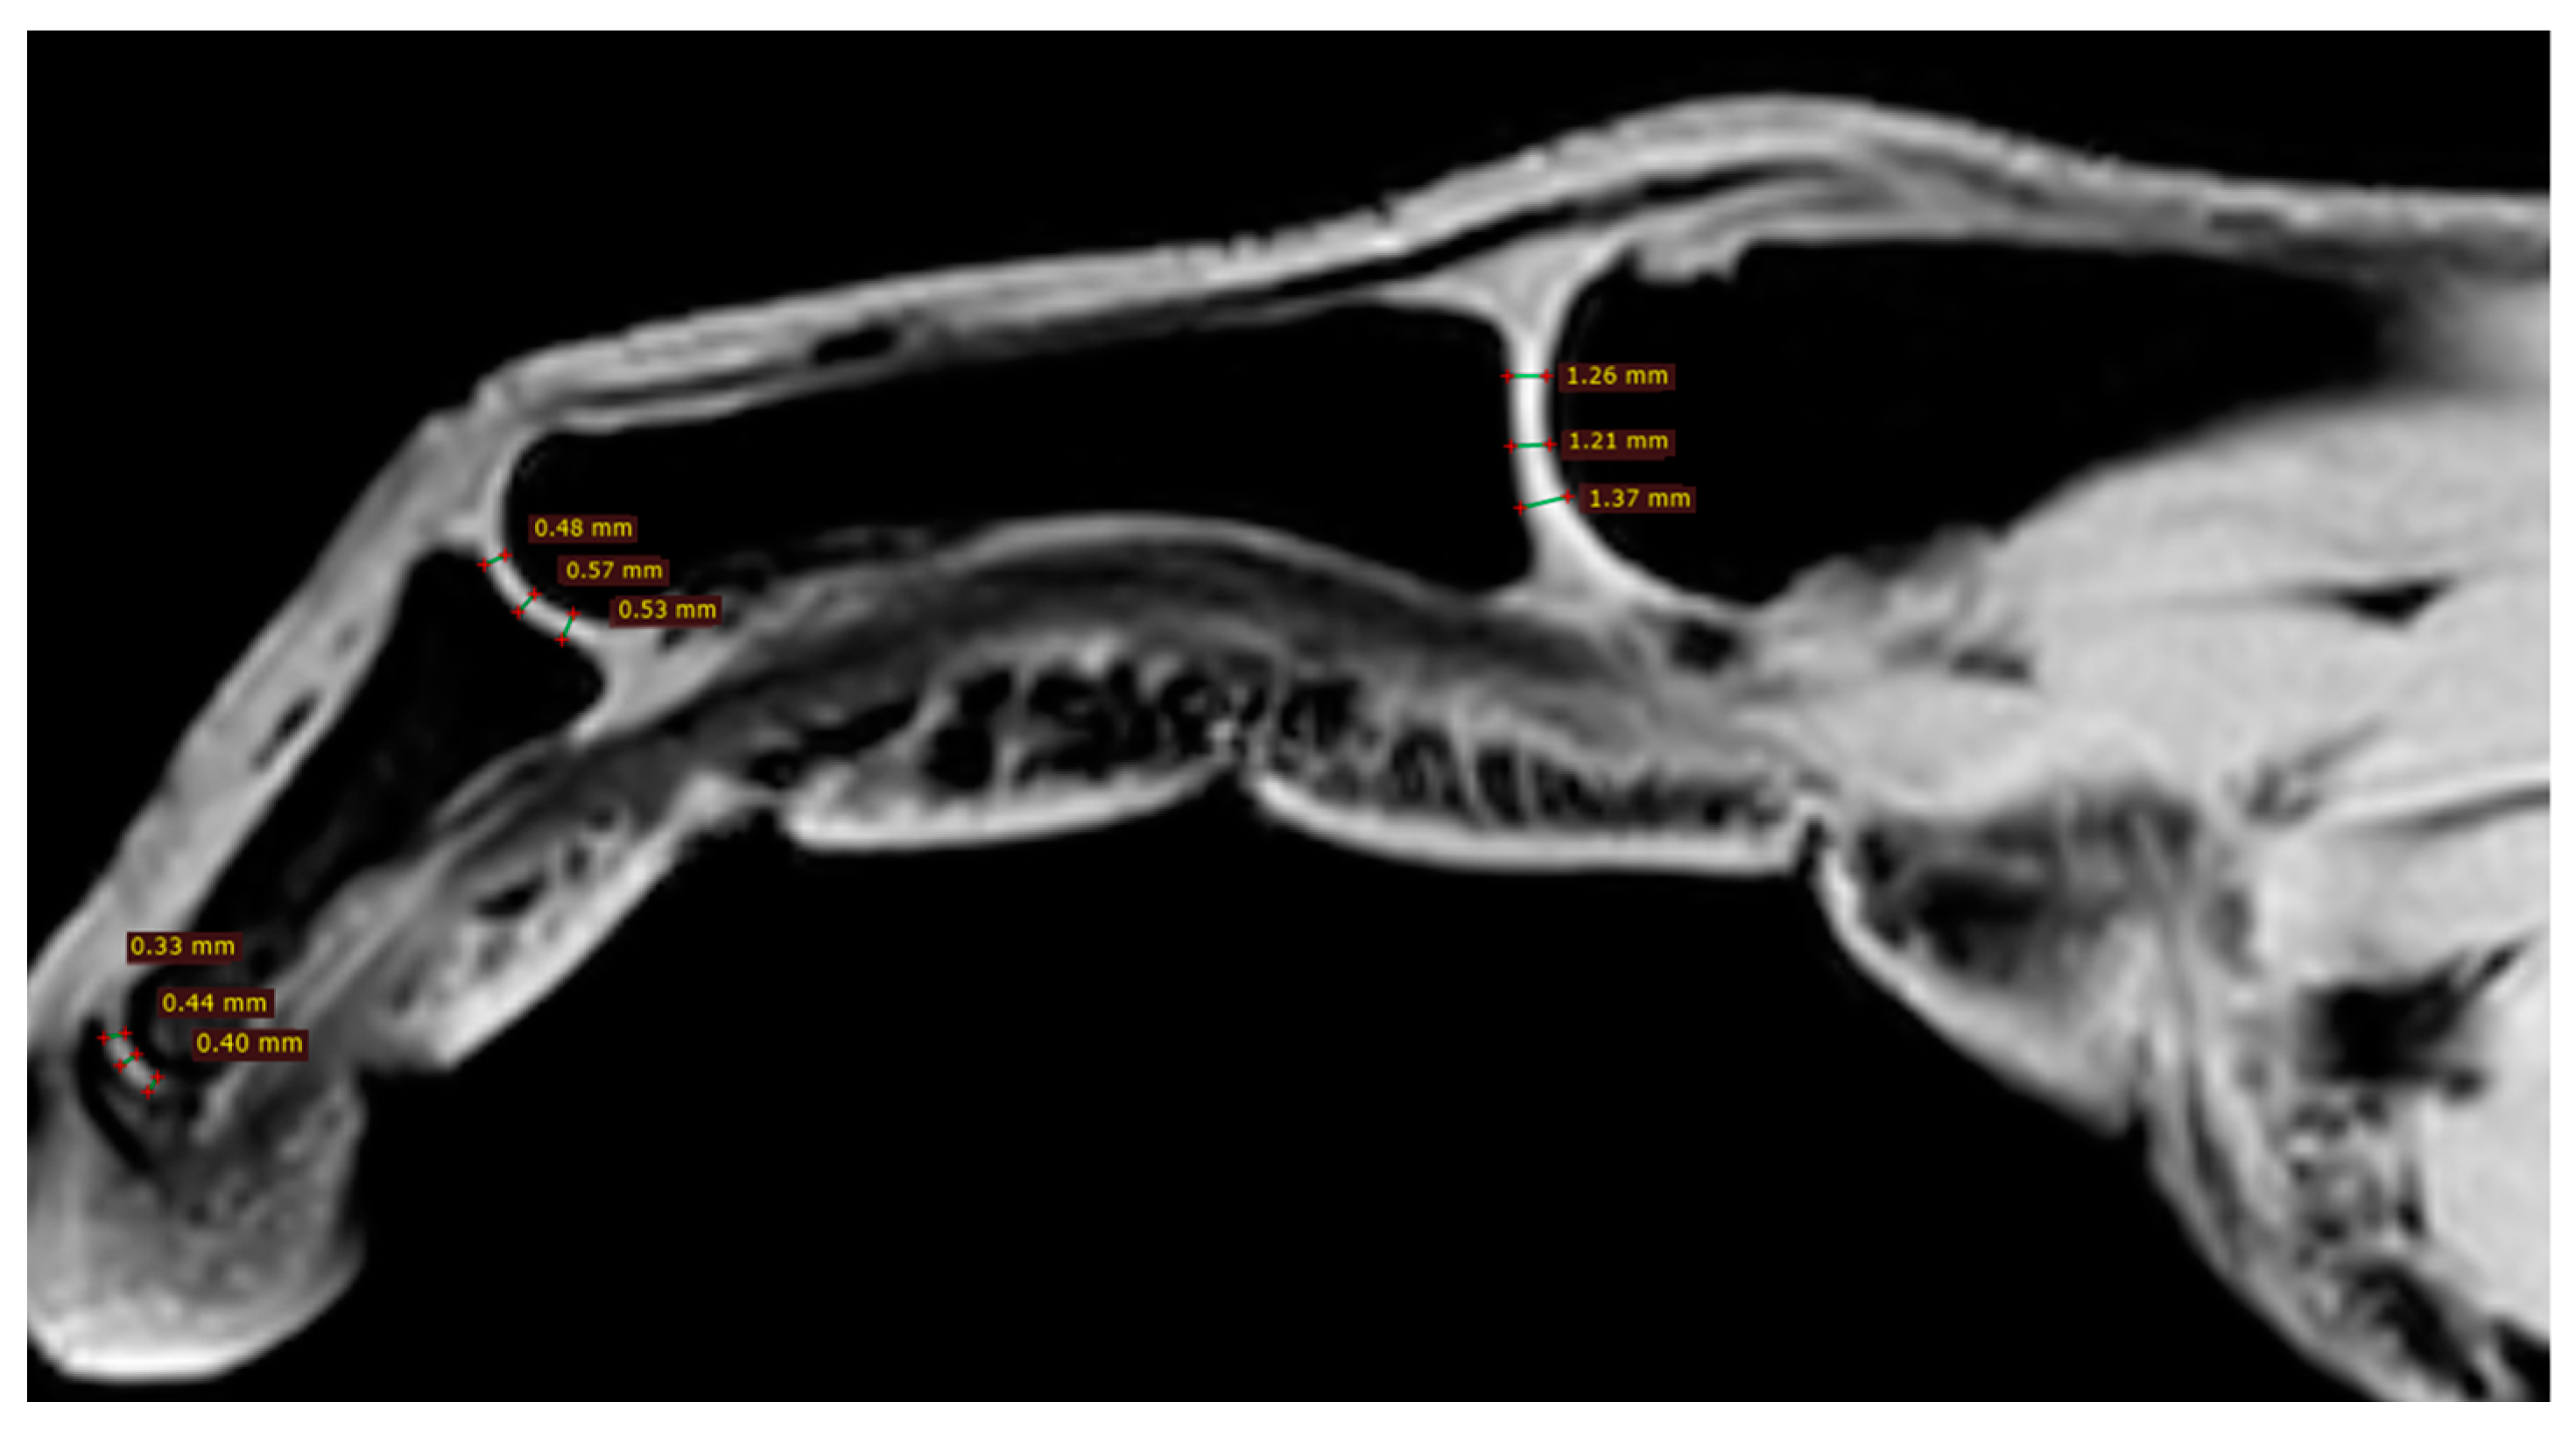

| Parameter | Acro-Osteolysis (11 Fingers) | Normal (89 Fingers) | p-Value |

|---|---|---|---|

| DPL | 4.9 (1.77) | 16.2 (2.33) | 0.0044 |

| DIPJct | 0.4 (0.04) | 0.8 (0.2) | 0.0034 |

| PIPJct | 0.5 (0.04) | 0.8 (0.2) | 0.0043 |

| MCPJct | 1.3 (0.2) | 1.2 (0.2) | 0.8554 |